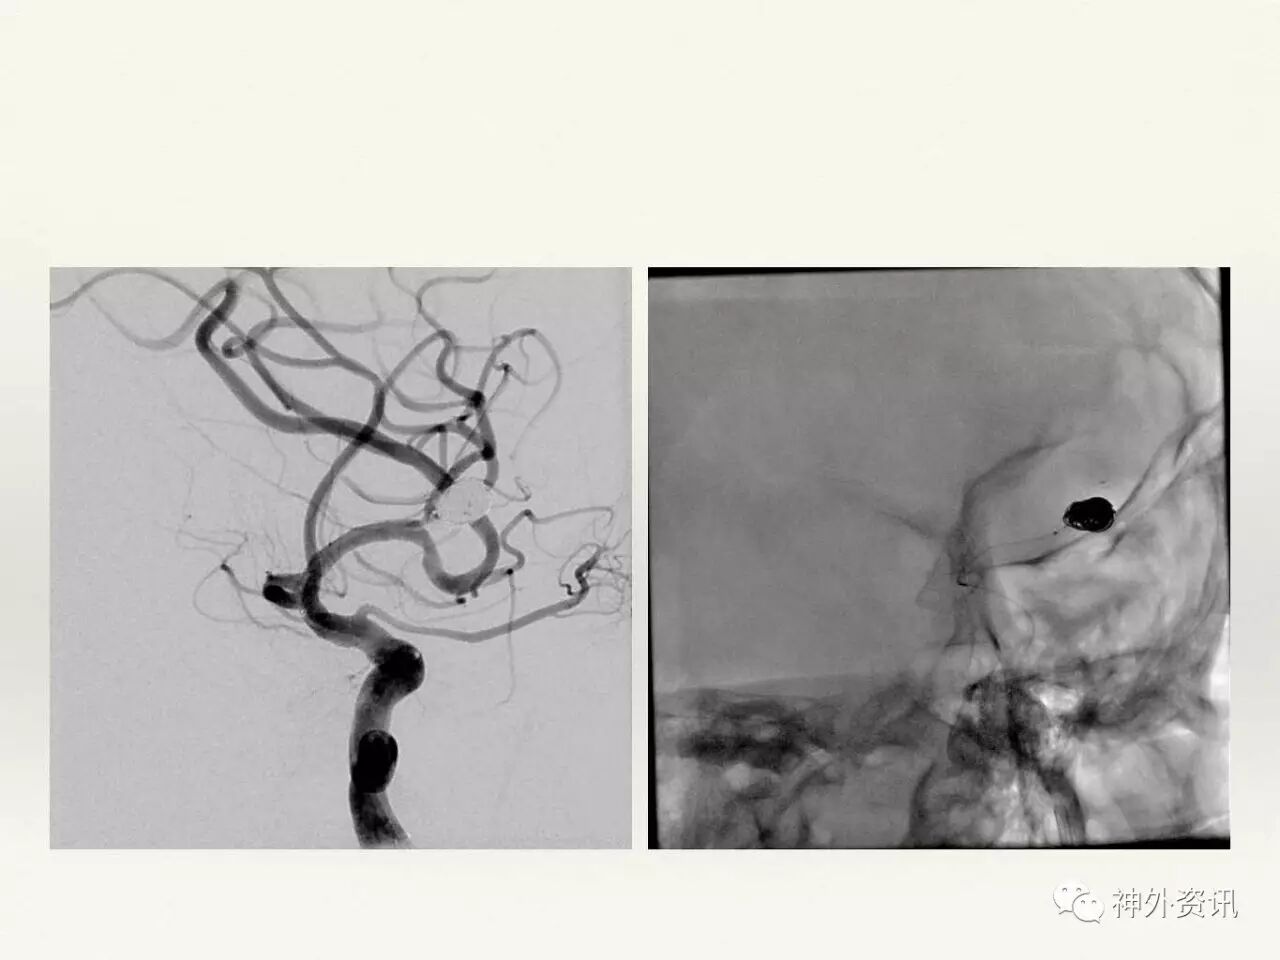

在东北地区率先开展了颈内动脉、大脑中动脉及基底动脉闭塞血管内再通、颅内动脉栓塞急性期取栓、血流导向装置治疗大型宽颈动脉瘤等,对颅内动脉瘤、动静脉畸形、颈动脉及颅内动脉狭窄、颈内动脉海绵窦瘘、硬脑膜动静脉瘘等外科治疗具有较深的造诣。完成脑血管造影8600余例,各类脑血管病介入手术共4500余例,动脉瘤、动静脉畸形、脑肿瘤、脑出血及脑外伤等外科手术1500余例。